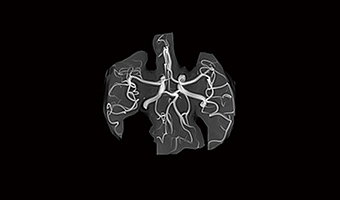

Application Images

Power Sense Fast Imaging System

Integrating conventional Sense and Compressed Sense technologies, the acquisition mode is optimized for fast acquisition, which improved scanning speed and image quality. Power sense acceleration technology is used to collect only a few sampling points in a short time, and construct a high-resolution image.